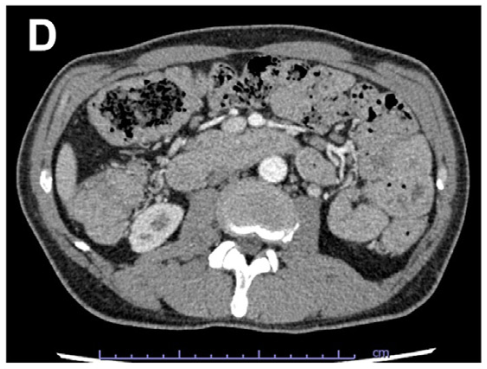

•影像学检查:腹部/盆腔增强CT或MRI和(或)肠道CT或MRI重建可观察到胃、小肠和结直肠肠壁增厚、多发息肉样病变,可用于评估胃肠道的受累情况、息肉的负荷程度、并发症的诊断等,有助于评估CCS的病情。CCS患者常伴随蛋白从肠道中丢失,核医学检查有助于明确肠道蛋白丢失。